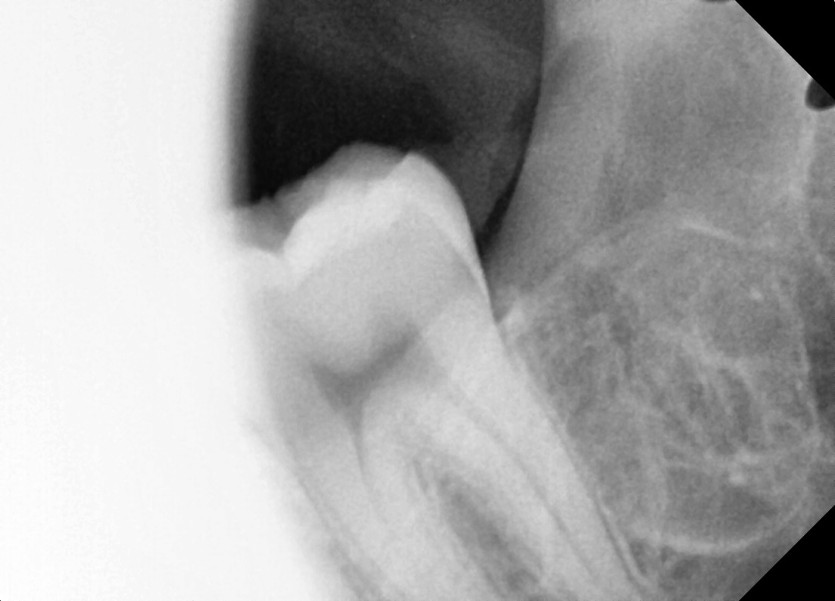

#28,38 사랑니 발치

구강 외과 전문의가 당일 발치했습니다.